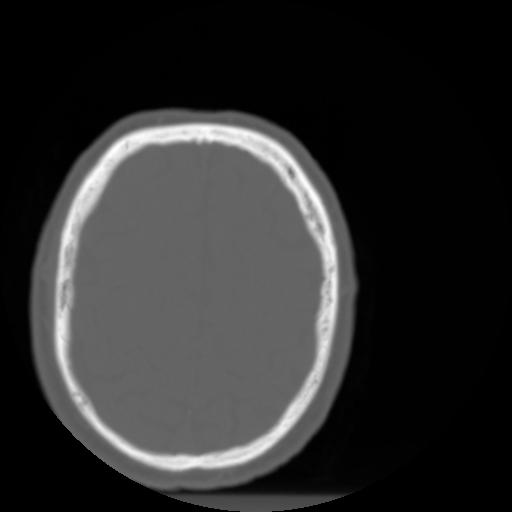

3 CEREBRO,,Axial,3.0,CEREBRO,,